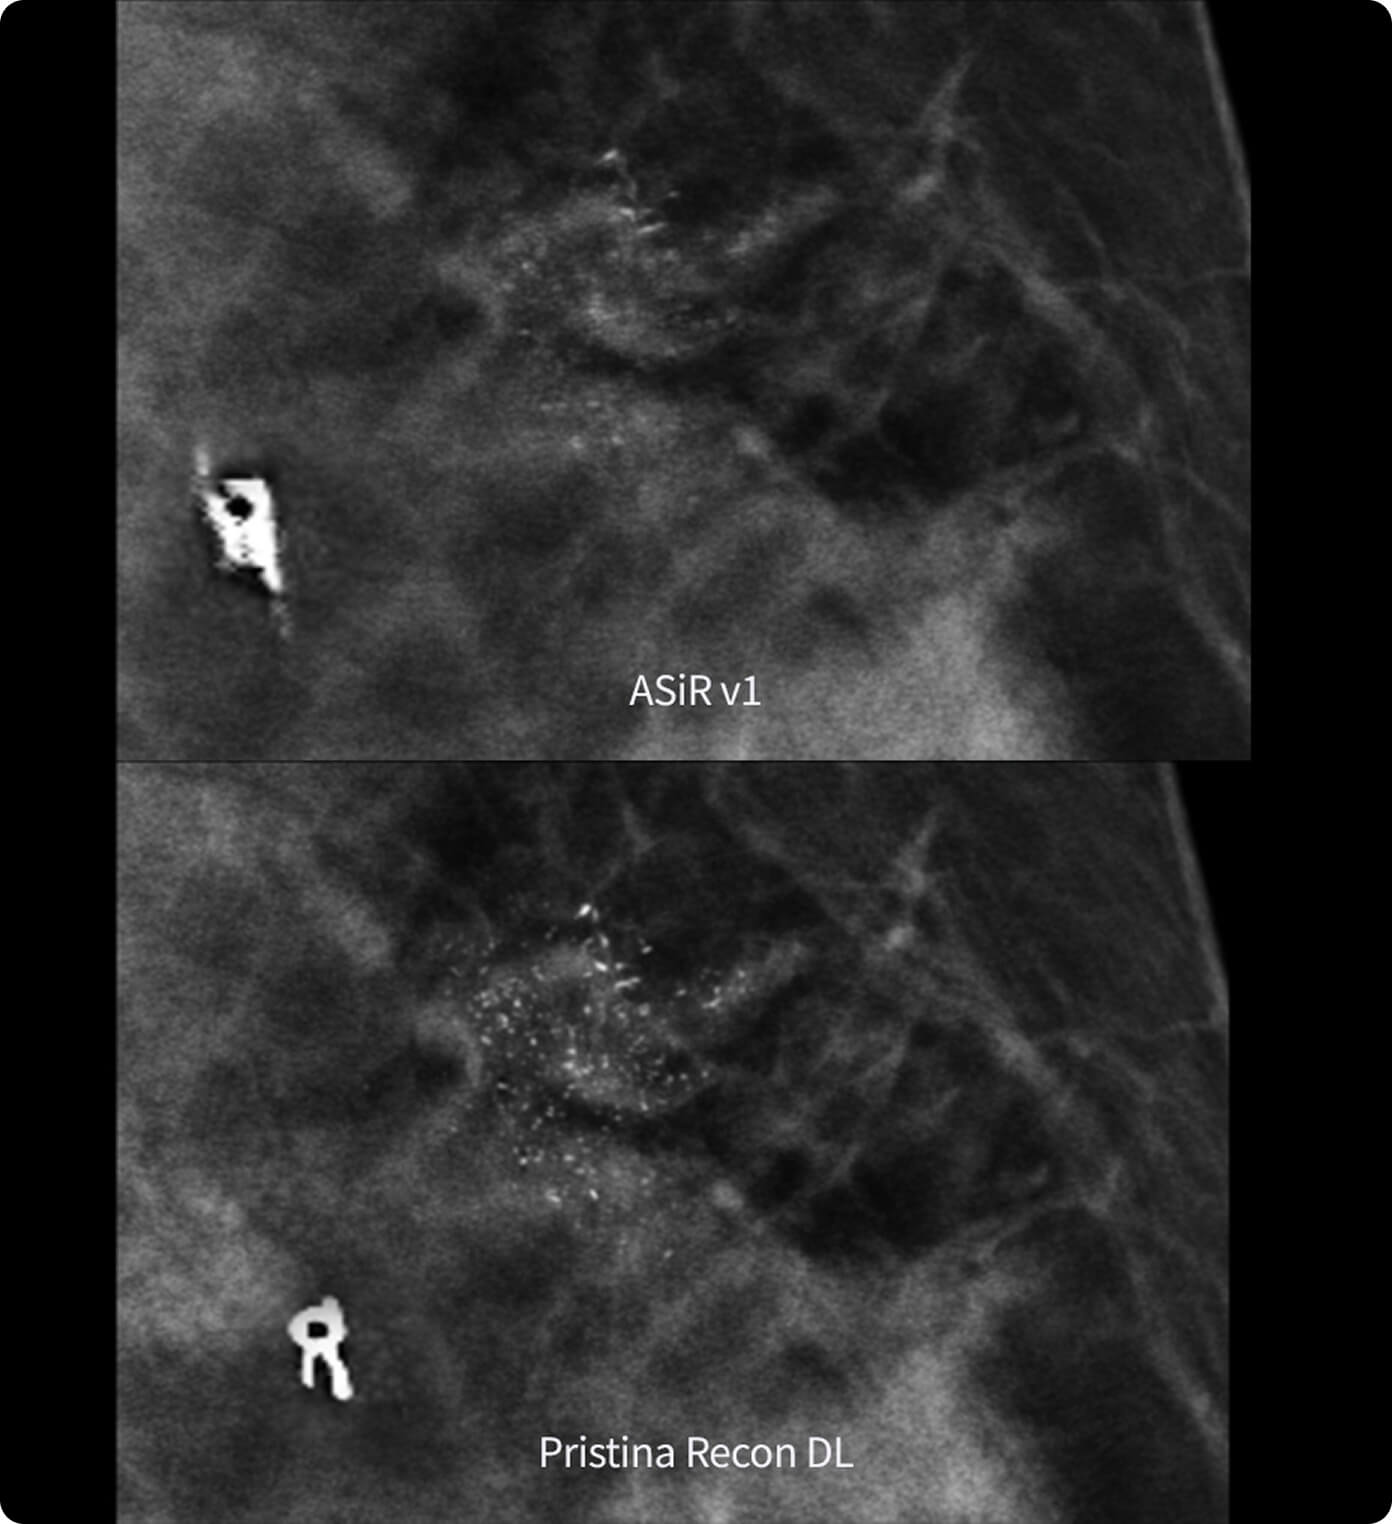

Met en évidence des détails fins tout en réduisant les artefacts et le bruit perçu¹

Dans la détection des foyers de microcalcifications à partir de données cliniques modélisées²

Sa technologie à double réseau de deep learning révèle des détails fins tout en réduisant les artefacts et le bruit perçu1,2, sans augmenter la dose.

L’amélioration est évidente : les radiologues interrogés préfèrent systématiquement sa netteté1,2 et la visibilité des lésions1,2.

1. Étude de préférence réalisée sur 140 cas d’étude avec 8 radiologues agréés MQSA, formés à l’évaluation de la qualité d’image clinique par l’ACR, comparant Pristina Recon DL à ASiR v1.

2. Évaluation des performances de lecture sur 19 680 lectures avec 8 lecteurs, utilisant des données cliniques modélisées, comparant Pristina Recon DL et ASiR v1.